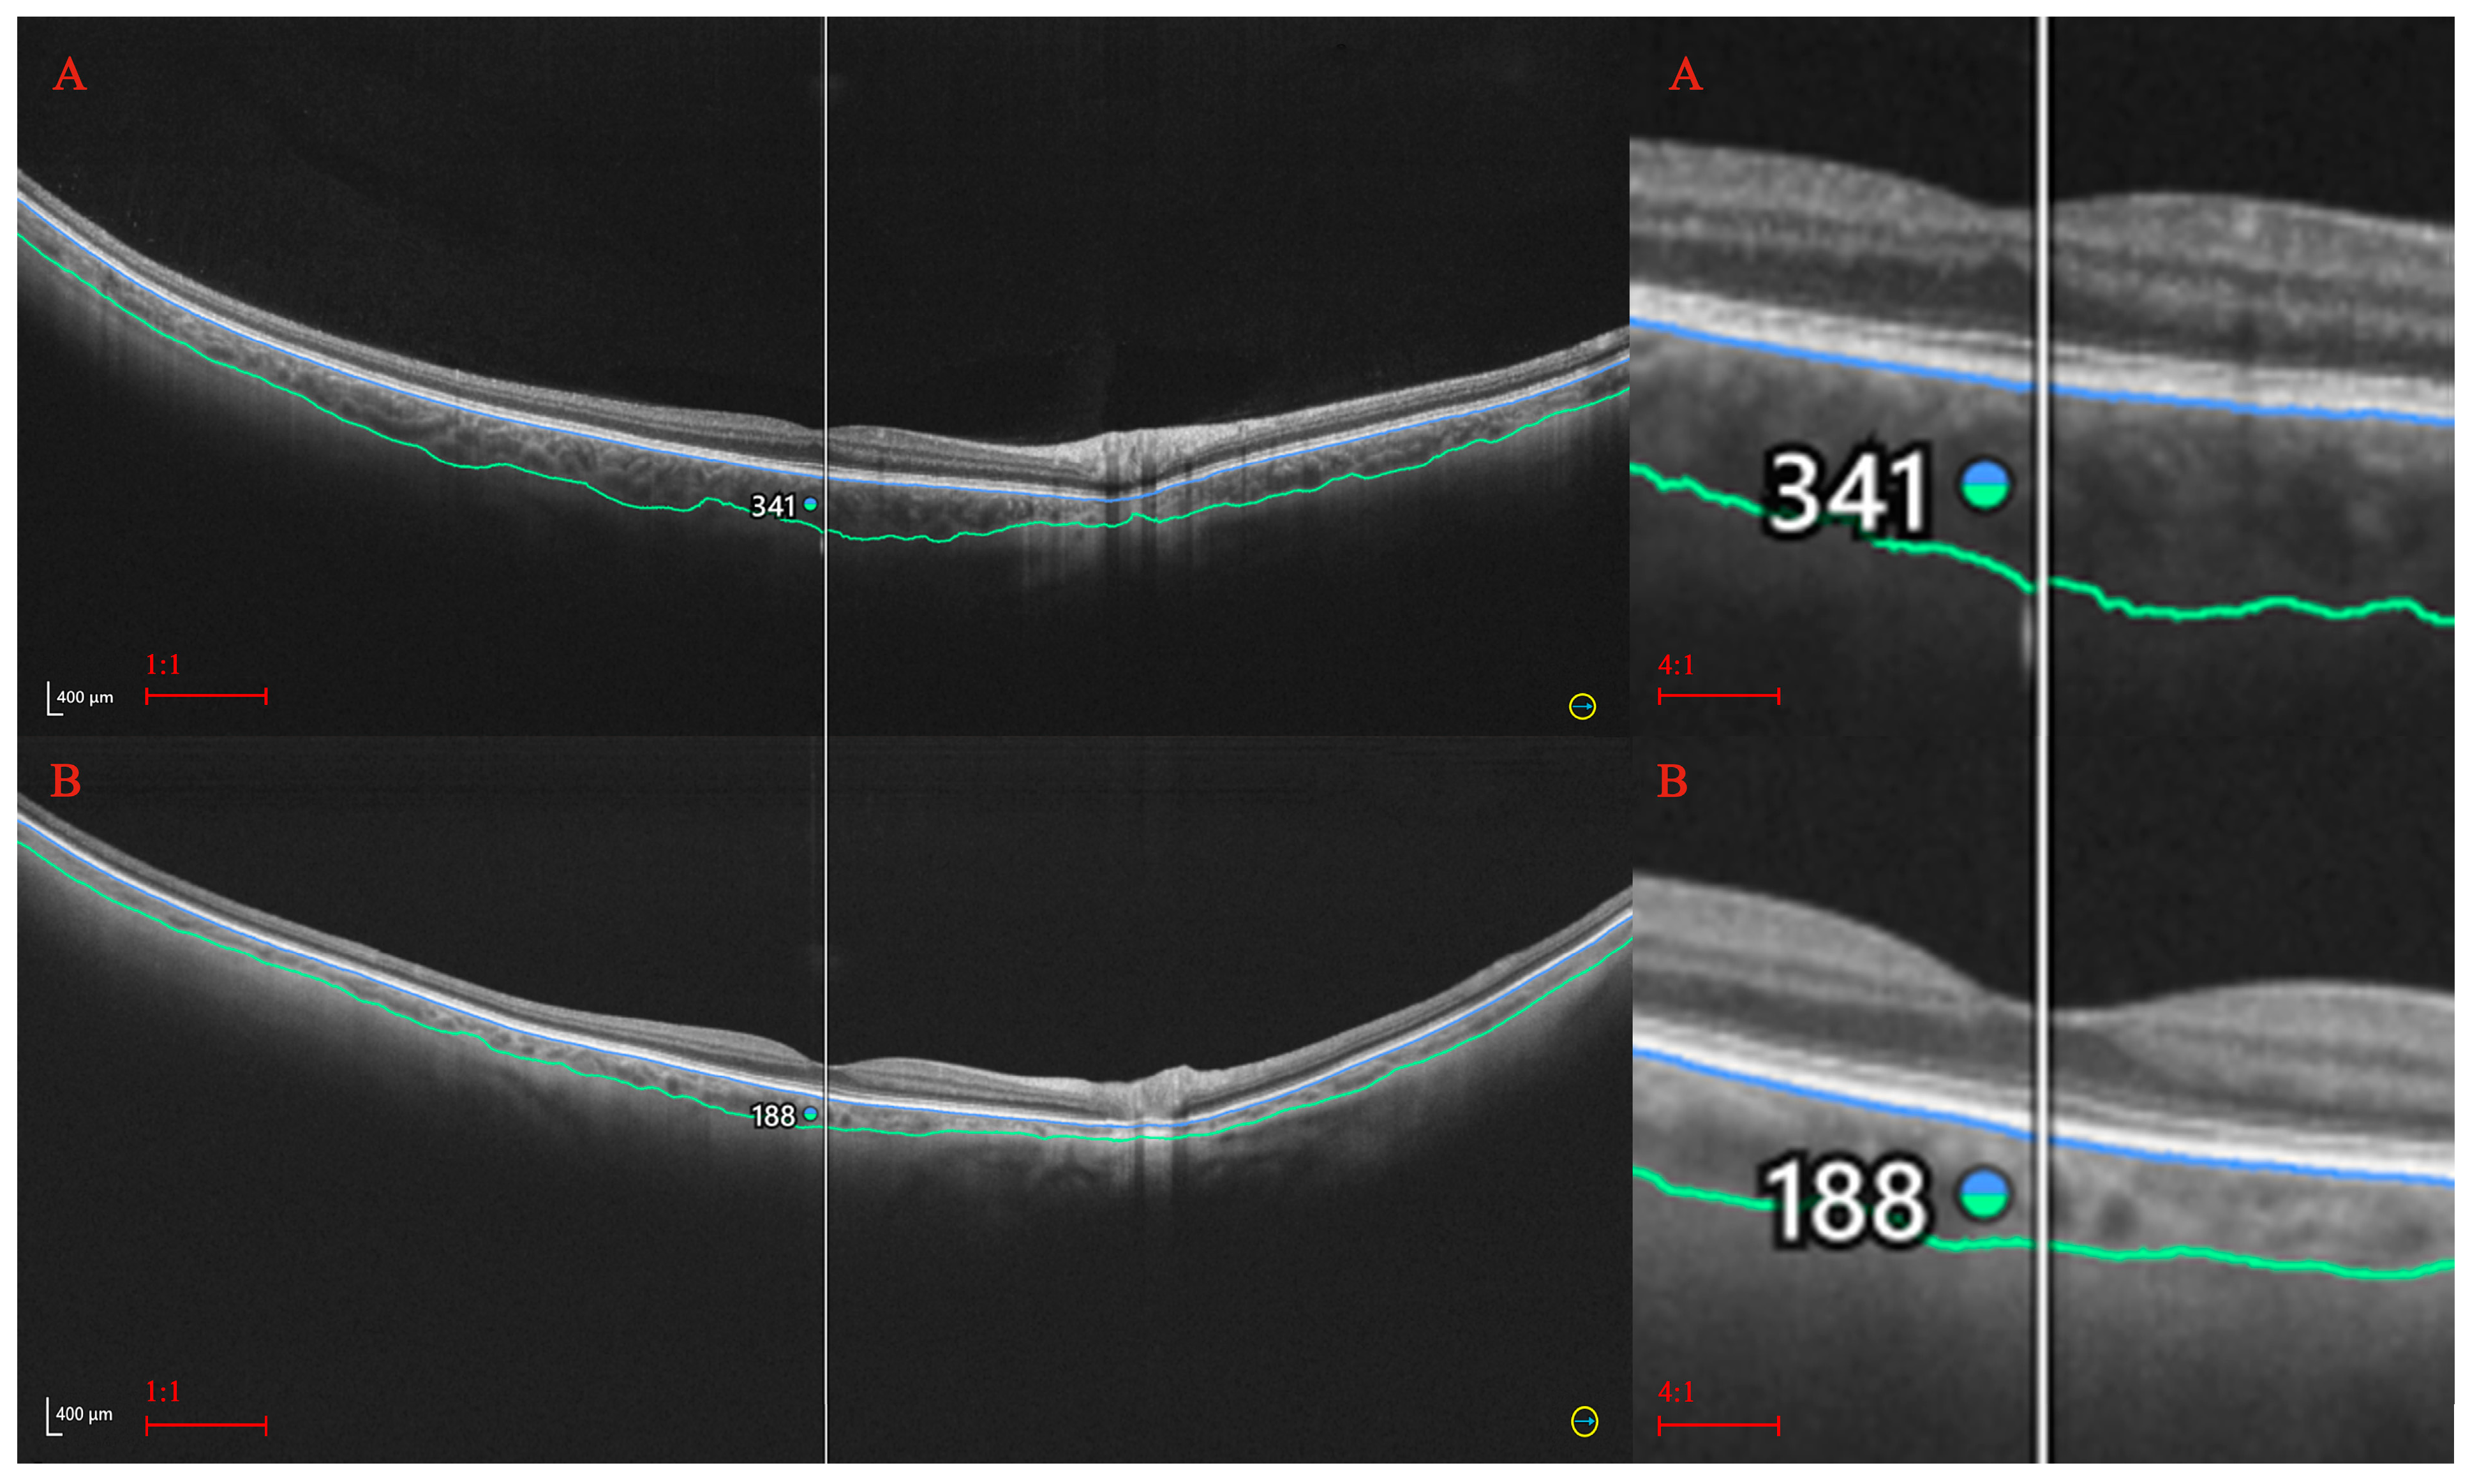

2. Materials and Methods